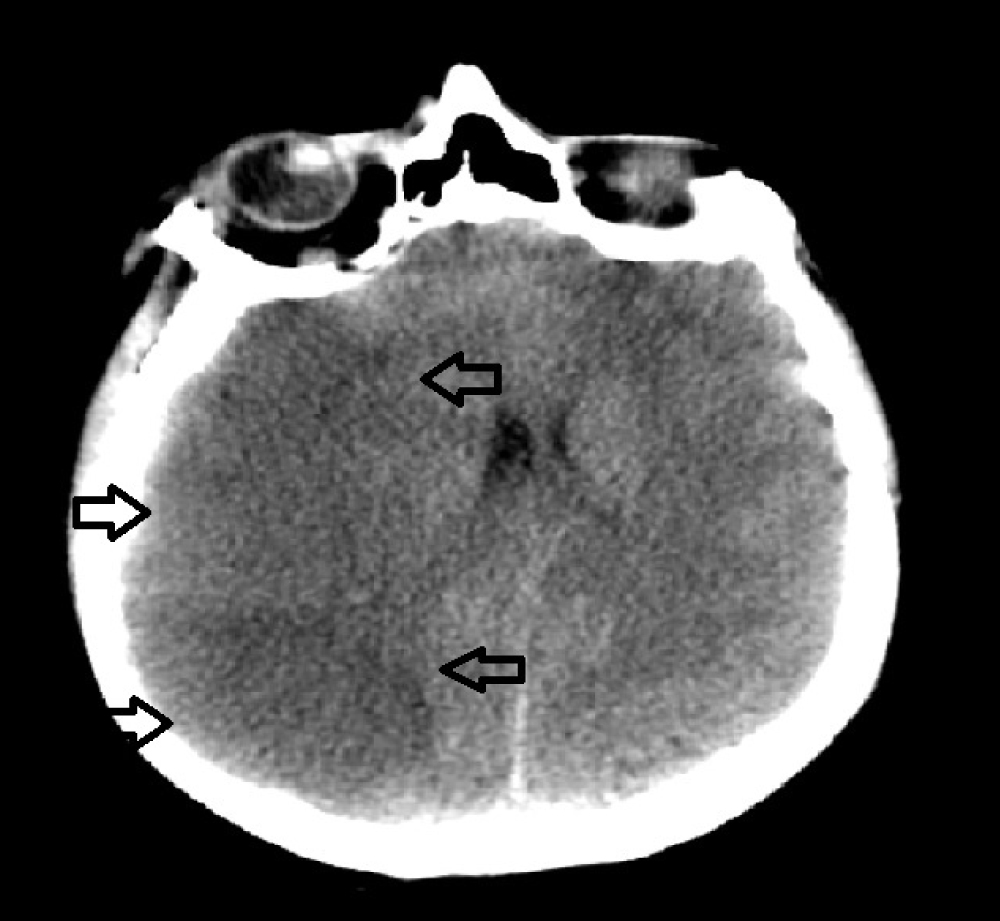

The second day after operation the patient had severe headache and became confused. GCS dropped to 12/15. An emergency cranial CT scan was perfomed and demonstated massive hypodensity areas in the right temporal and frontoparietal lobes, which suggested a decrease in perfusion as well as right side global brain edema and ischemic infarct (Figure 3). As the patient's neurologic condition was deteriorating we perfomed an emergency rightside cranial decompression. Mannitol treatment was applied to the patient for brain edema. The blood test results after first operation didnt show the very high number of leukocytes, 40,000/μL (leukocytosis) to cause thrombosis as the patient had CML. Increase of leukocytes is frequent after surgery. Nevertheless, flow cytometry was performed by consulting the patient with hematology. In flow cytometry, an atypical cell group with a total of 90% localized CD34/CD117 blast was found on CD45. The patient admitted in the blast phase of CML. After the operation the patient didnt recover soon and remained under ventilator support. The patient's neurological examination continued to deteriorate. We perfomed cranial CT scan and suprisingly observing both massive cerebral and cerebellar infarcts (Figure 4). This strongly suggests that rather than direct vascular compression by the tumor there must be other strong vasoactive agents secreted by the tumor itself which leads to massive vasospasms. In the postoperative period, fresh frozen plasma and nimodipine were given to the patient for the treatment of vasospasm.

Figure 3: Post-operative axial CT scan showing right temporoparietal infarcts and brain edema. View Figure 3

Figure 4: a) Axial CT scan showing massive right temporoparietal infarcts after cranial decompression; b) CT scan showing low density area in the right cerebellar. View Figure 4